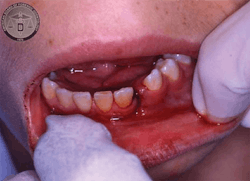

In addition to your clinical diagnosis or differential diagnosis, some additional documentation is recommended here. Take photos (intra- and extraoral) using a ruler or scale next to injuries to show size. Even a cotton roll or periodontal probe can be used, because it is a size that is reproducible and consistent. Coins have been used in some cases for a size reference because that was all that was on hand, and it works! Include quoted remarks, comments, explanations made by the child and by the parent/guardian/caretaker, and take very descriptive notes on hard-and-soft tissue findings and any comments on the observable demeanor of the child and adult. Remember that this might be the only chance to document an injury before it heals.